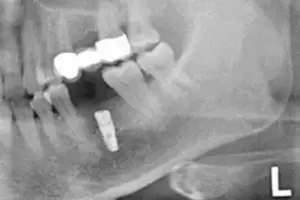

Am Ende des Eingriffs wird von mir direkt und vor Ort nochmal mittels Röntgenaufnahme die korrekte Position des Implantats überprüft. Dadurch stelle ich auf einem zusätzlichen Weg für Sie abschließend sicher, dass ich Ihren Implantat-Körper perfekt in den Knochen eingesetzt habe.

Bild 4: Röntgenkontrolle der Implantatsposition nach erfolgtem Eingriff

Nach der Röntgenbildaufnahme geht es zurück in eines meiner Behandlungszimmer. Herr F. bekommt das Röntgenbild gezeigt und erläutert, sodass er sich selbst davon überzeugen kann, dass der Implantat-Körper einwandfrei in seinen Kieferknochen eingesetzt wurde. Siehe Bild 4. Das Zahnfleisch wird nun über den frisch eingesetzten Implantat-Körper gelegt und vernäht. Siehe Bild 5.